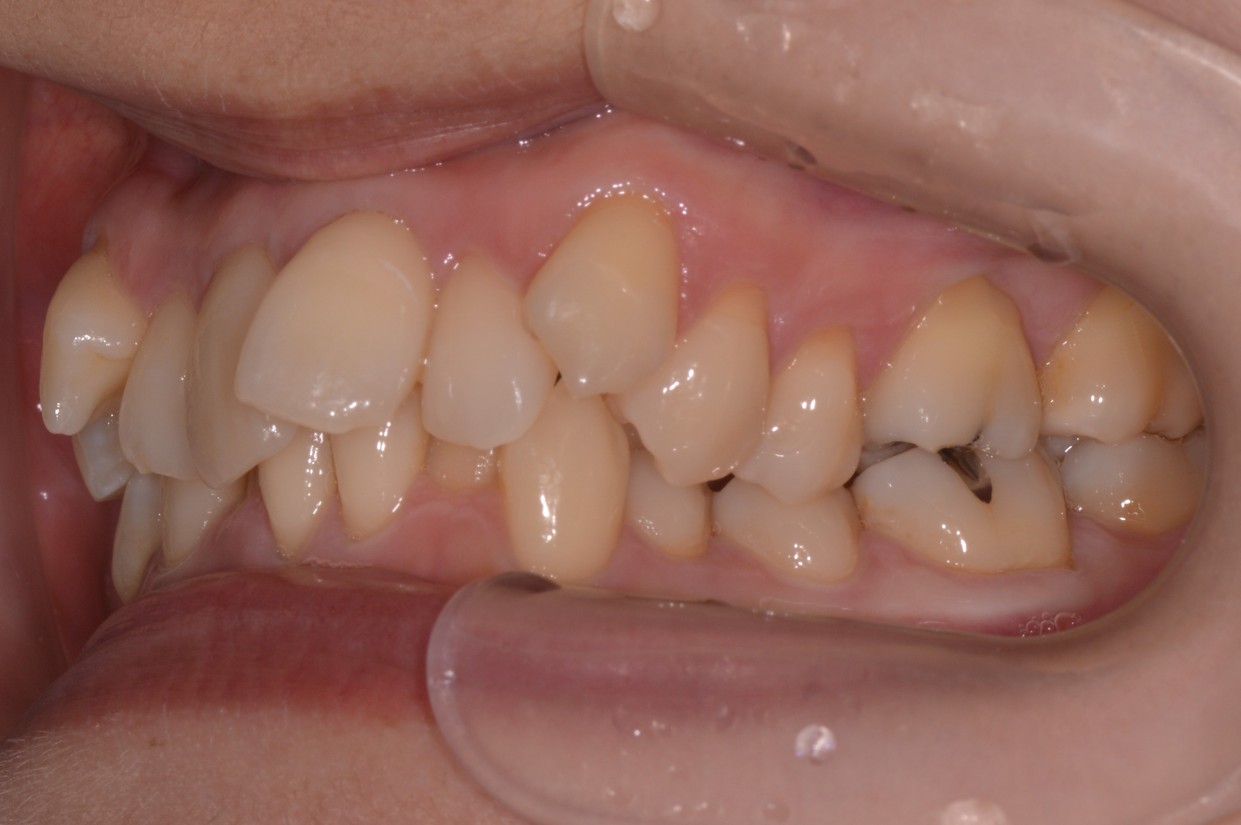

症例2

| 項目 | 詳細 |

|---|---|

| 患者様データ | 30代 女性 |

| 来院時の主訴 | 「右上の、内側に生えている歯が邪魔。」 |

| 矯正法 | 上の歯2本、下の歯2本、親知らず3本を抜歯しての矯正 |

| 通院期間 | 3年6ヶ月 |

| 治療費 | 総額:1,230,000円(税抜) 【内訳】 精密検査50,000円、メタルワイヤー矯正800,000円、月に1度の調整料5,000円、後戻り防止のリテーナー35,000円×2 |

| リスクと副作用 |

①歯を動かす事による痛みがあります。また、装置に慣れるまでは、口内炎ができやすいです。 ②歯肉が退縮するリスクがあります。装置が全ての歯に付くので、ハミガキが難しくなります。 ③長期的なメインテナンスが必要 |

| ここがこだわりのポイント!☝ | こちらの患者様は上の歯が1本内側に生えていましたが、奥歯の噛み合わせの方が問題でした。ハサミ状咬合といい、奥歯が極端に外側に向いており、下の歯と噛み合っていない状態でした。ハサミ状咬合は長期的にみると、前歯に大きな負担がかかったり、磨きにくい事による虫歯や歯周病になりやすいなどのリスクがあります。治療期間はかかりましたが、見た目の良さだけでなく、機能的にも改善しました。 |